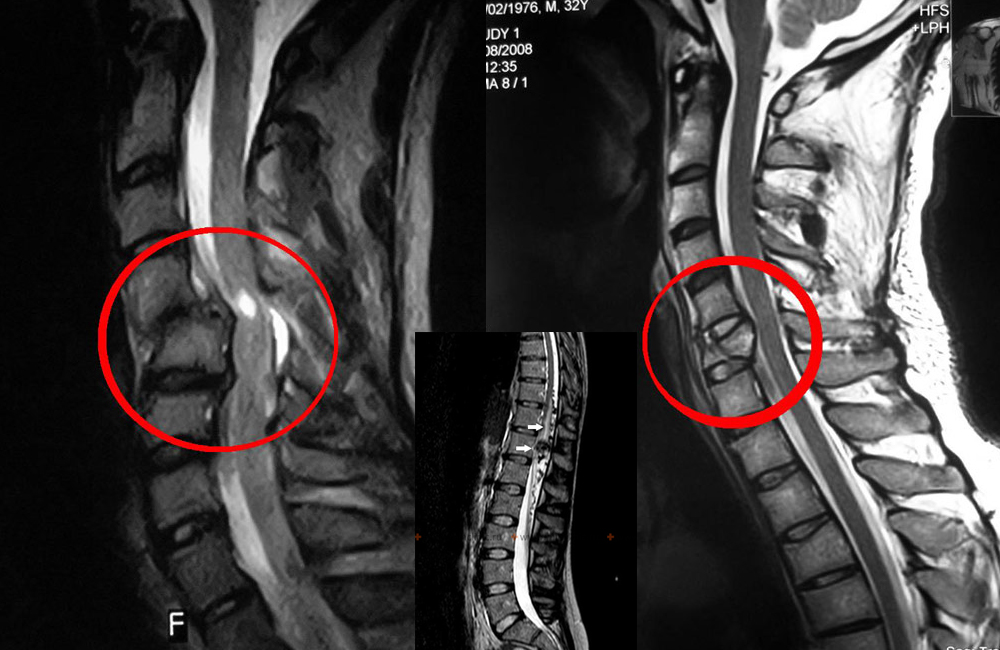

- рентгенография полости черепа, височно-нижнечелюстного сустава, шейного отдела позвоночника;

- МРТ или КТ шеи и головы.